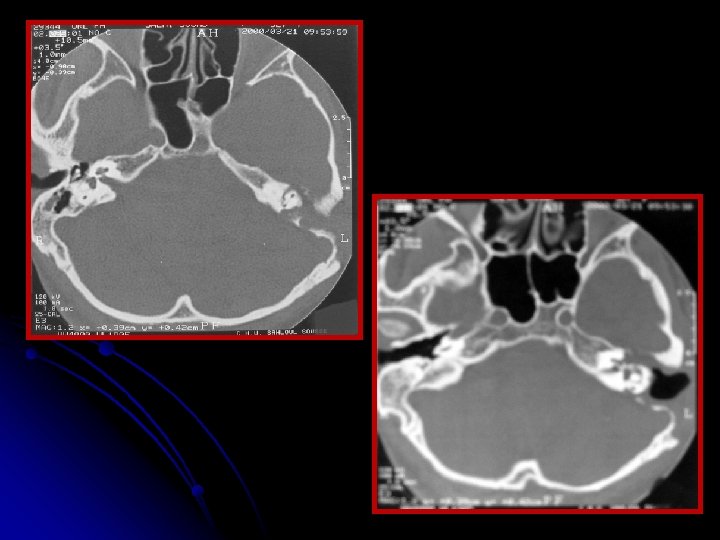

ØLe scanner des rochers montrait un cholestéatome qui contourne le labyrinthe et s'étend jusqu‘au CAI et au golfe de la jugulaire. ØLa patiente a eu dans un 2ème temps opératoire, une voie transcochléaire avec comblement de la cavité par de la graisse abdominale a été réalisée. ØLes suites opératoires étaient simples. ØRecul sans récidive : 4 ans.

Imagerie : diagnostic positif+++ • La TDM en coupes millimétrées en incidences axiale et coronale permet une appréciation précise de la destruction osseuse. • Cette destruction peut être due à une érosion de l’os par effet de pression entraînant une ischémie, à une hyperactivité ostéoclastique.

• La TDM objective une lacune polycyclique à contours arrondis, de nature avasculaire. • Elle précise l'extension et apprécie les refoulements dure-mériens. • Elle permet également de faire le diagnostic différentiel avec d’autres processus pathologiques intrapétreux